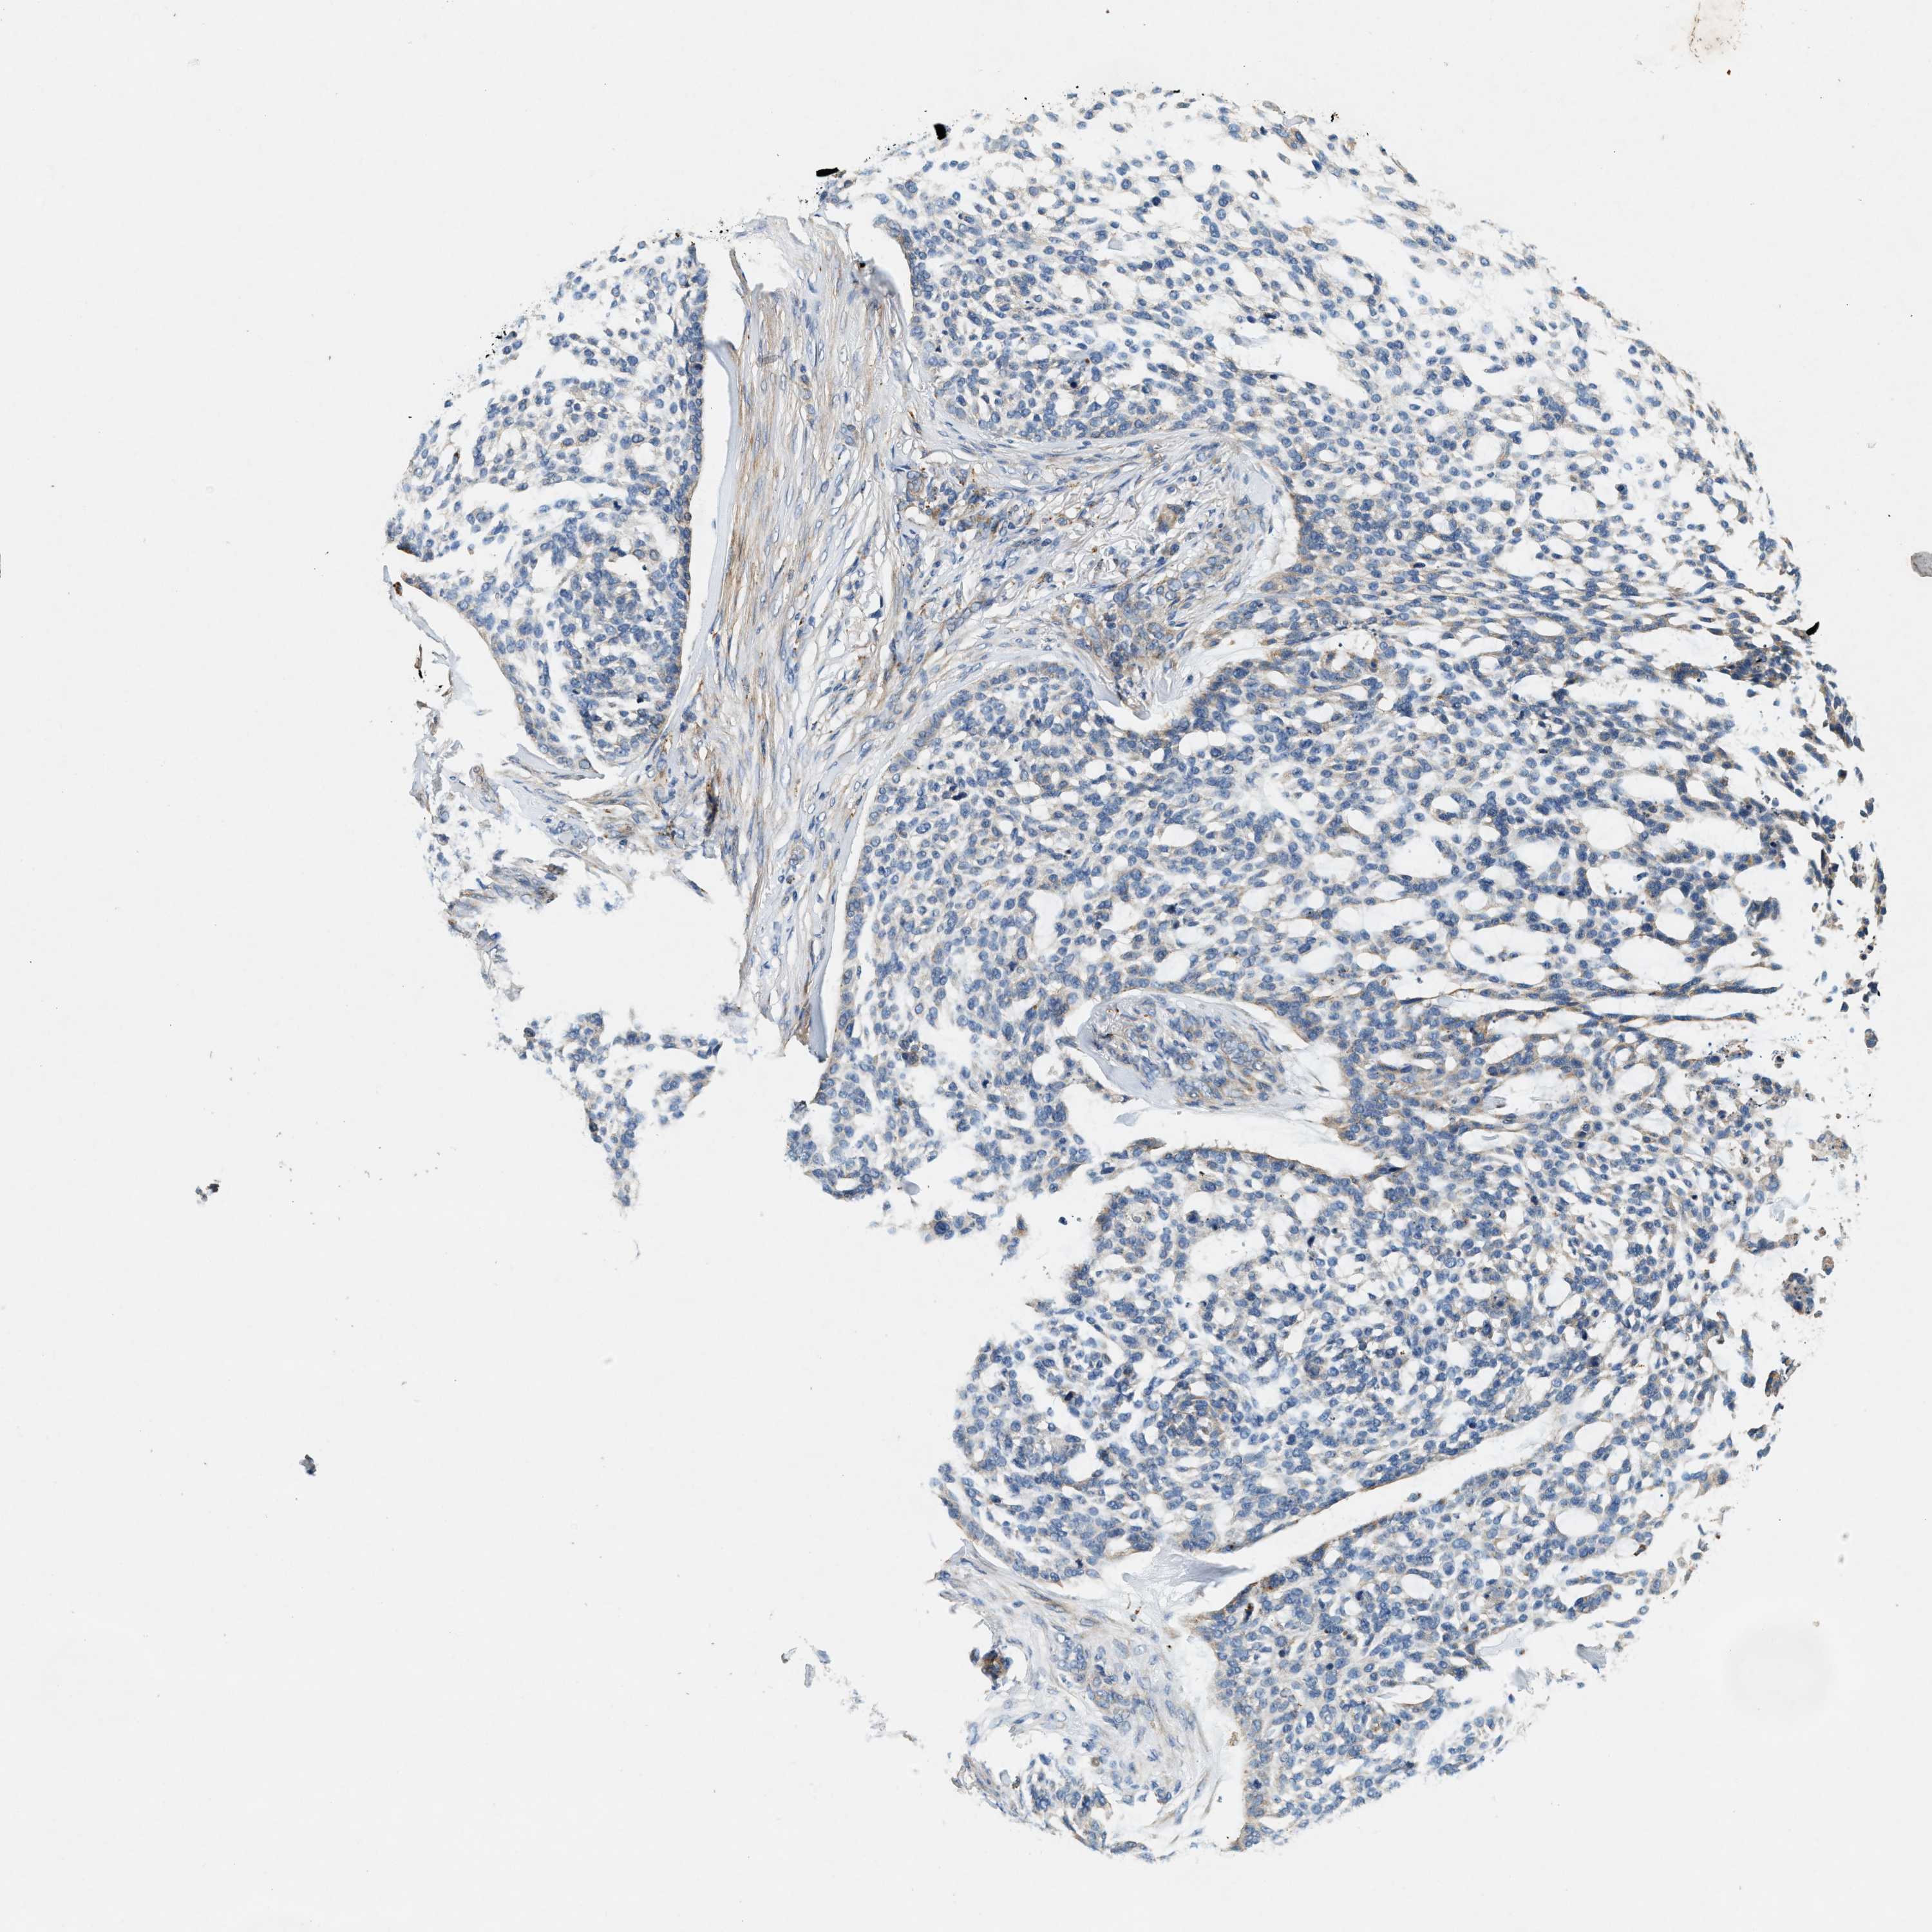

Basal cell and squamous cell cancer

SKIN CANCER - Protein expressioni

A mouse-over function shows sample information and annotation data. Click on an image to view it in a full screen mode. Samples can be filtered based on level of antibody staining by selecting one or several of the following categories: high, medium, low and not detected. The assay and annotation is described here.

Antibody stainingi

Antibody staining in the annotated cell types in the current human tissue is reported as not detected, low, medium, or high, based on conventional immunohistochemistry profiling in selected tissues. This score is based on the combination of the staining intensity and fraction of stained cells.

Each image is clickable and will lead to virtual microscopy that enables deeper exploration of all samples and also displays staining intensity scores, fraction scores and subcellular localization as well as patient and tissue information for each sample.

Antibody HPA016758

Squamous cell carcinoma, metastatic, NOS

Squamous cell carcinoma, NOS